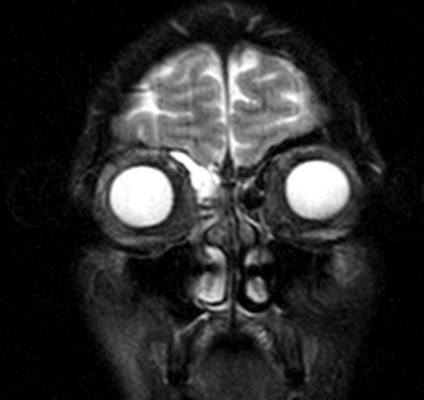

Магнитно-резонансное изображение измененной лобной пазухи